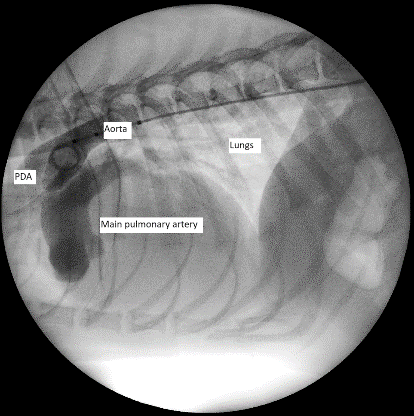

Echocardiographic visualisation of the PDA is the most common diagnostic tool (Figure 2).

In dogs with left-to-right PDA, the defect can be indirectly appreciated by the presence of a continuous turbulent flow in the main pulmonary artery. Secondary changes linked to left-to-right PDA include left atrial and ventricular dilation with or without mitral regurgitation and possible signs of left-sided CHF. The systolic function of the left ventricle is usually preserved, and the pulmonary arteries are dilated. Pulmonic insufficiency is also common. Measurements of the ostium and the ampulla are often required to plan surgical procedures.

In dogs with right-to-left PDA, right-sided enlargement and hypertrophy are often found because of PHT. Right-sided heart failure may show with pericardial, pleural or abdominal effusion. The PDA is usually difficult to visualise as there is no continuous flow in the main pulmonary artery (as happens in left-to-right). This is due to the reduced pressure gradient leading to low velocities. For this reason, dogs with right-to-left PDA do not present with a murmur. However, a bubble study, which involves the injection of agitated saline solution in a cephalic vein, would show bubbles in the descending aorta (due to the shunting of blood away from the lungs that normally reabsorb them).